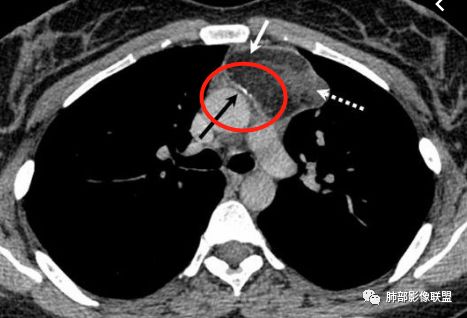

1.CD钙化不支持,一般条状短棒状为主,小结节

也有,这么大的钙化少见,分叶也太明显。

2.异位甲状腺:发病率低,强化太弱,一般来说异位甲状腺强化达100多

3.神经鞘瘤:深分叶,这么大钙化罕见

所以胸腺瘤首选,其次畸胎瘤,SFT

病    理:

胸腺瘤

王兆宇老师:畸胎瘤总有油脂物质密度,块状钙化少见,环状钙化多见,头结节骨化多见,畸胎瘤钙化不在中间。

纵隔或胸膜伴钙化疾病谱(吴婧):A:异位甲状腺——最常见,甲状腺癌非常容易钙化,一般与甲状腺相连,平扫因为摄碘,CT值很高,增强后则明显增高。B:畸胎瘤——脂肪、牙齿密度可识别。一般多发年轻30岁左右,钙化特点为块状钙化少见,环状钙化多见,钙化不在中间(偏心钙化)。很少强化或轻度强化                            (王兆宇老师)C:CD透明细胞型——一般钙化为条状钙化,病灶形态通常为圆形、光滑、规则、全实性,不软所以不会见缝就钻,也不会坏死,强化非常高。D:胸腺瘤——一般30岁以后,容易钙化为A、AB、B1型,B2型以后钙化少见。钙化特点为大块状钙化、中间钙化。E:SFT——钙化会沿着胸膜的长轴生长。

F:神经鞘瘤——也会钙化,但明显少于以上疾病。G:脉管瘤——年轻人,点状静脉石。

胸腺瘤钙化

大部分钙化还是包膜钙化和条状,结节状钙化,团块状钙化也比较少。位置中央,周围都可以。